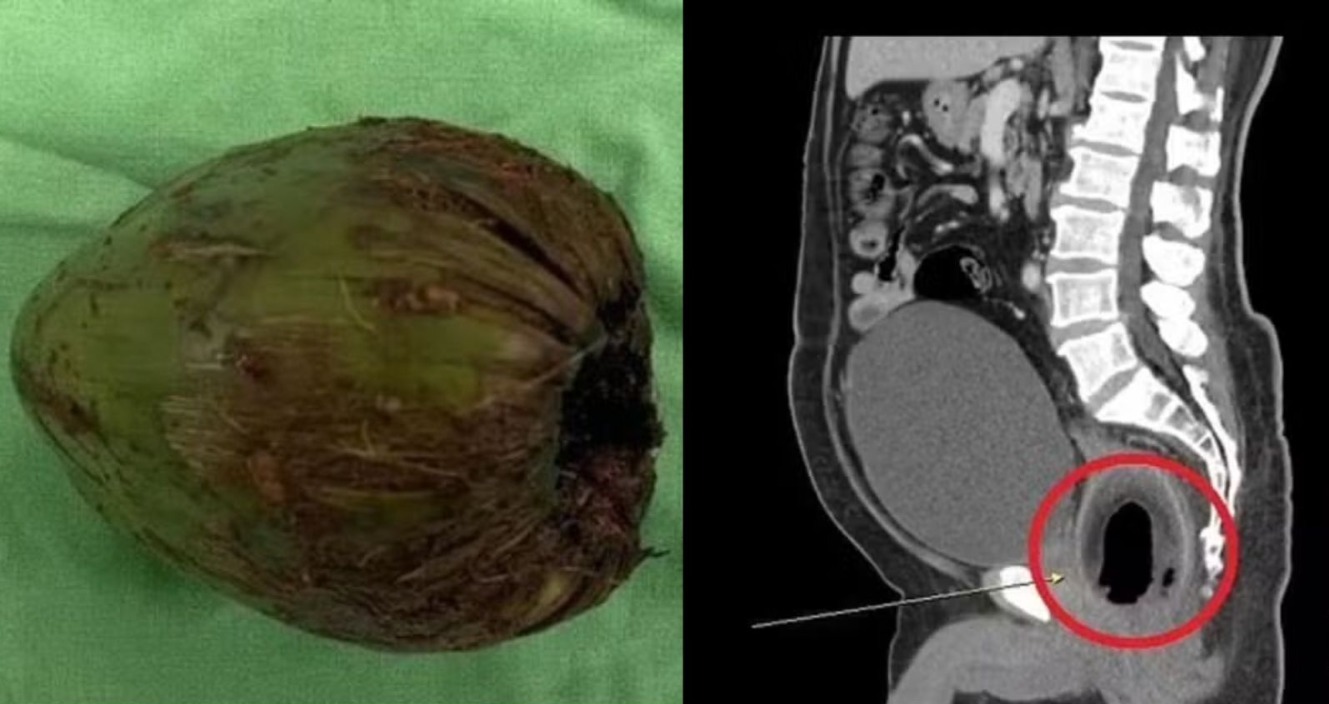

Um homem de 56 anos, em Taiwan, foi hospitalizado após enfiar um coco no ânus para o próprio prazer sexual. A fruta ficou presa no corpo do senhor, que começou a passar mal.

O taiwanês, que teve seu nome preservado, passou a sentir muitas dores no abdômen e não conseguia defecar nem urinar. Dois dias depois, ele correu para o hospital e passou por uma cirurgia para a retirada.

O coco, que media 11 cm, estava localizado no reto e pressionava a uretra, impedindo-o de ir ao banheiro.

“Este foi um caso muito raro. O paciente teve sorte de ainda estar vivo. Felizmente, ele não sofreu danos internos graves. Dissemos para não fazer isso novamente. O paciente admitiu que colocou o coco no reto em busca de estímulo“, disse Chen Zhiyi, segundo o “Daily Star“.